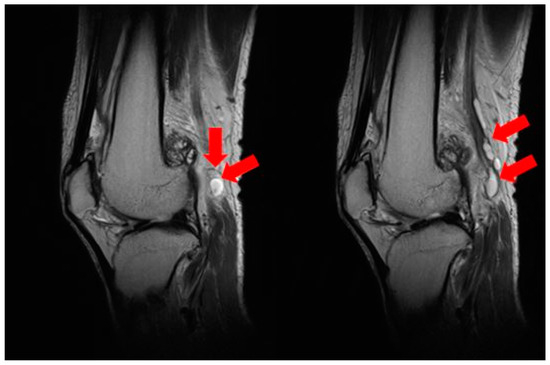

2.1. Preoperative Evaluation